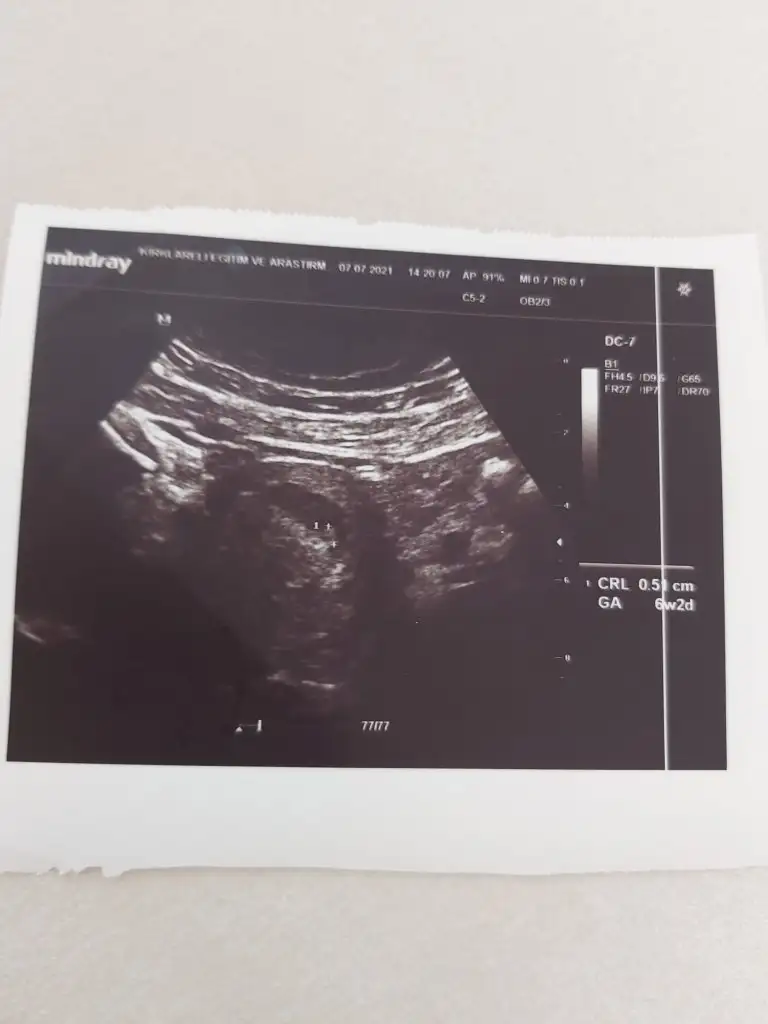

6 haftalık gebeyim.Kesem sol tarafta. Bebekte kesenin en soluna yerleşmiş sizce kız mı erkek mi😊😊 heyecandan bekleyemiyorum

Karından ultrason.ama doktor bakarken de sadece sol tarafima baktı

Önemli olan plesantanın konumu bebekte plesantada sağda görünüyor. (Karından Ultrasonda bakıldığında görüntü ters ayna görevi görür, yani evet aslında bebek kesenin solunda ama karından bakıldığında tam tersi görünüyor. İnşallah anlatabilmişimdir) Benim tahminim bebeğin cinsiyeti kız:KK51:Allah sağlıkla kucağına almayı nasip etsin inşallah:nazar::KK200: